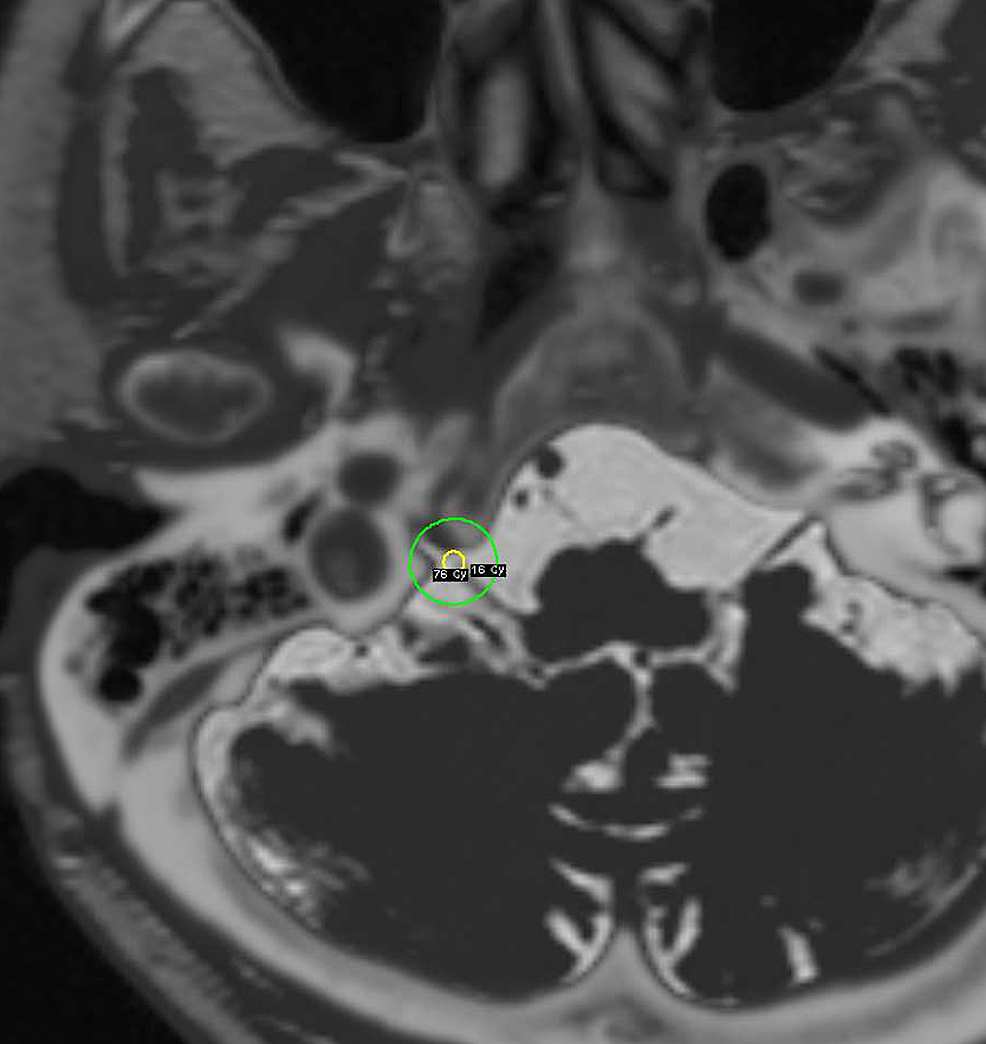

Gamma Knife Radiosurgery For Trigeminal Neuralgia Current Concepts and Gamma Knife For Trigeminal Neuralgia In this insightful article, highly esteemed consultant neurosurgeon mr jonathan hyam shares his expertise on the procedure. The gamma knife irradiates the trigeminal nerve for around 40 minutes during treatment. The smallest of the collimators on the gamma knife (4mm) is used to irradiate the proximal trigeminal nerve at its entry into the pons (superior part of. The head is. Gamma Knife For Trigeminal Neuralgia.

Second Gamma Knife Treatment for Trigeminal Neuralgia Anterior Target Gamma Knife For Trigeminal Neuralgia Gamma knife stereotactic radiosurgery is, compared with surgical treatment, a less invasive treatment option for patients with trigeminal neuralgia (tn). Gamma knife stereotactic radiosurgery is a revolutionary treatment for patients with trigeminal neuralgia. In this insightful article, highly esteemed consultant neurosurgeon mr jonathan hyam shares his expertise on the procedure. It is associated with a low risk of facial paresthesias,. Gamma Knife For Trigeminal Neuralgia.